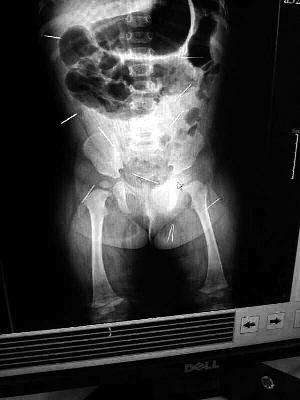

“要不是當(dāng)初那幾個(gè)紅點(diǎn),可能到現(xiàn)在我們還不知道孩子身體里有鋼針!”昨天,在兒童醫(yī)院住院處,萱萱爸爸范先生稱,日前原本很愛笑的萱萱突然變得有些焦躁,一抱起來就哭,孩子母親偶然間在萱萱屁股上發(fā)現(xiàn)了幾個(gè)小紅點(diǎn)兒,原以為是蚊蟲叮咬,就醫(yī)結(jié)果卻讓人不寒而栗。“醫(yī)院拍出的片子上,萱萱的體內(nèi)有12根鋼針,插滿臀部、腹腔、骨盆等各個(gè)部位。”范先生介紹,因?yàn)殇撫樢焉钊塍w內(nèi),要是孩子不哭鬧,他們很難發(fā)現(xiàn)。

北京晨報(bào)記者了解到,目前體內(nèi)的12根鋼針多分布在孩子的臀部,一根在腹部,其余3根在胸腔附近,其中一根很接近心臟(如圖)。“因?yàn)楹⒆犹,醫(yī)生們害怕取針的時(shí)候?qū)λ斐蓚,在胸腔附近?針可能會(huì)威脅她的生命”。